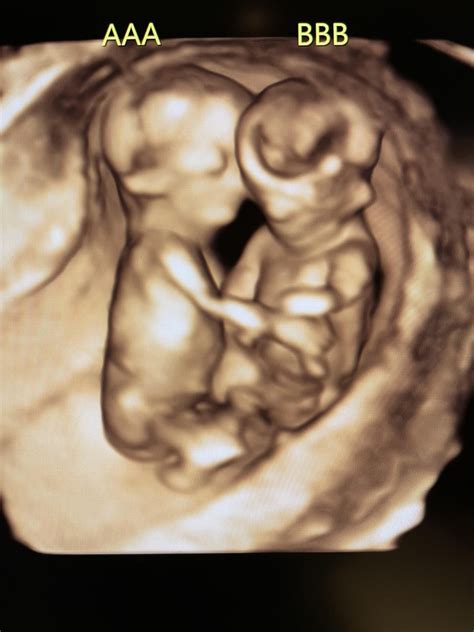

• momo twins ultrasound pictures

• momo twins ultrasound